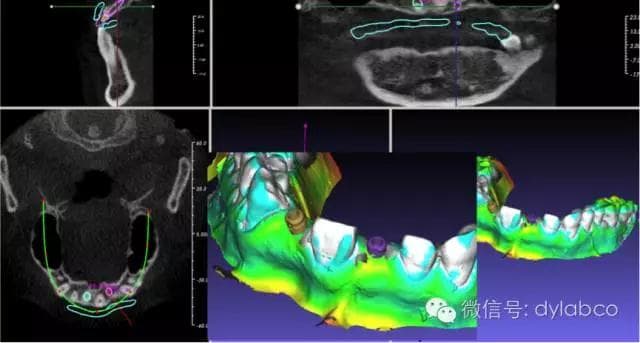

摘要:ezBond致力于3D数字化正畸相关技术的创新与研发,拥有全新发明专利的间接矫正技术,数字化排牙搭配计算机托槽精准定位,以快捷且精准的直丝弓治疗方式和CBCT安全控根设计,辅助正畸医师在临床操作上追求最理想的状态,藉此缩短患者治疗时间,减少不舒适感,并结合个性化3D打印技术和正畸定位导板,释放医师临床操作时间,达到医师与患者双赢的治疗。

主讲人:黄正和教授:现职为东莞定远陶齿制品有限公司正畸部技术顾问,台湾定邦数位股份有限公司总经理。ezBond 3D矫正定位导板发明人。2006年开始进行3D矫正定位导板之研发工作,远赴韩国正庆大学访问学习正畸相关技术并特别与Dr.Kyung学习托槽间接粘着相关技术,之后获得多项矫正定位发明专利认证,2010年开始受大陆正畸权威傅明魁大师之邀,多次赴中国进行专业课程教学。在舌侧矫正及数字化正畸领域有多项全世界的专利,并成功的将这些专利转化为临床高级数位化正畸产品,为正畸牙医师提供了无与伦比的精准定位及排牙方案。 3.开始到结束时间:2016.10.28 09:00-10:30 提问交流10分钟 数字化种植/主题二: 1.题目:《数字化种植导板的发展和应用》《The development and Application of Digital Implant Surgical Guide》 摘要:报告内容包括数值化种植导板和种植设计软件的发展,种植软件的功能需求,国际上主要软件的简单回顾,软件系统评估的主要因素,数字化种植工作流程与医技配合,该美(GuideMia)种植设计软件的功能介绍,特别是全口种植中的解决方案和应用,以及种植导板技术的展望。 2.主讲人:高飞 博士 高飞博士:西安电子科技大学博士,美国GuideMiaTechnologies的创办人。领导设计和开发了GuideMia 的核心技术和种植和正畸软件。高飞博士2008-2010任美国最大的义齿公司GlidewellDental Laboratories 软件开发部经理,负责公司在图像处理,CAD,PACS等领域的软件系统的开发。2005-2008期间,高飞在美国南加州Multi-DimensionalImaging Co.任首席软件工程师,从事3D医学图像处理软件的研究开发和应用。在此之前高飞长期担任UGS (西门子 PLM)CAD 建模系统构架组的主任软件工程师和部门经理,领导完成了一系列UG NX软件项目,对大量汽车,航空航天和船舶项目有深远影响。UGS有很多CAD/CAM业界广为人知的技术都是在他领导下开发完成或完善的。高飞博士还是1997-1999德国洪堡学者, 1994-1996上海交通大学博士后。 3.开始到结束时间 2016.10.28 10:40-11:50提问交流10分钟